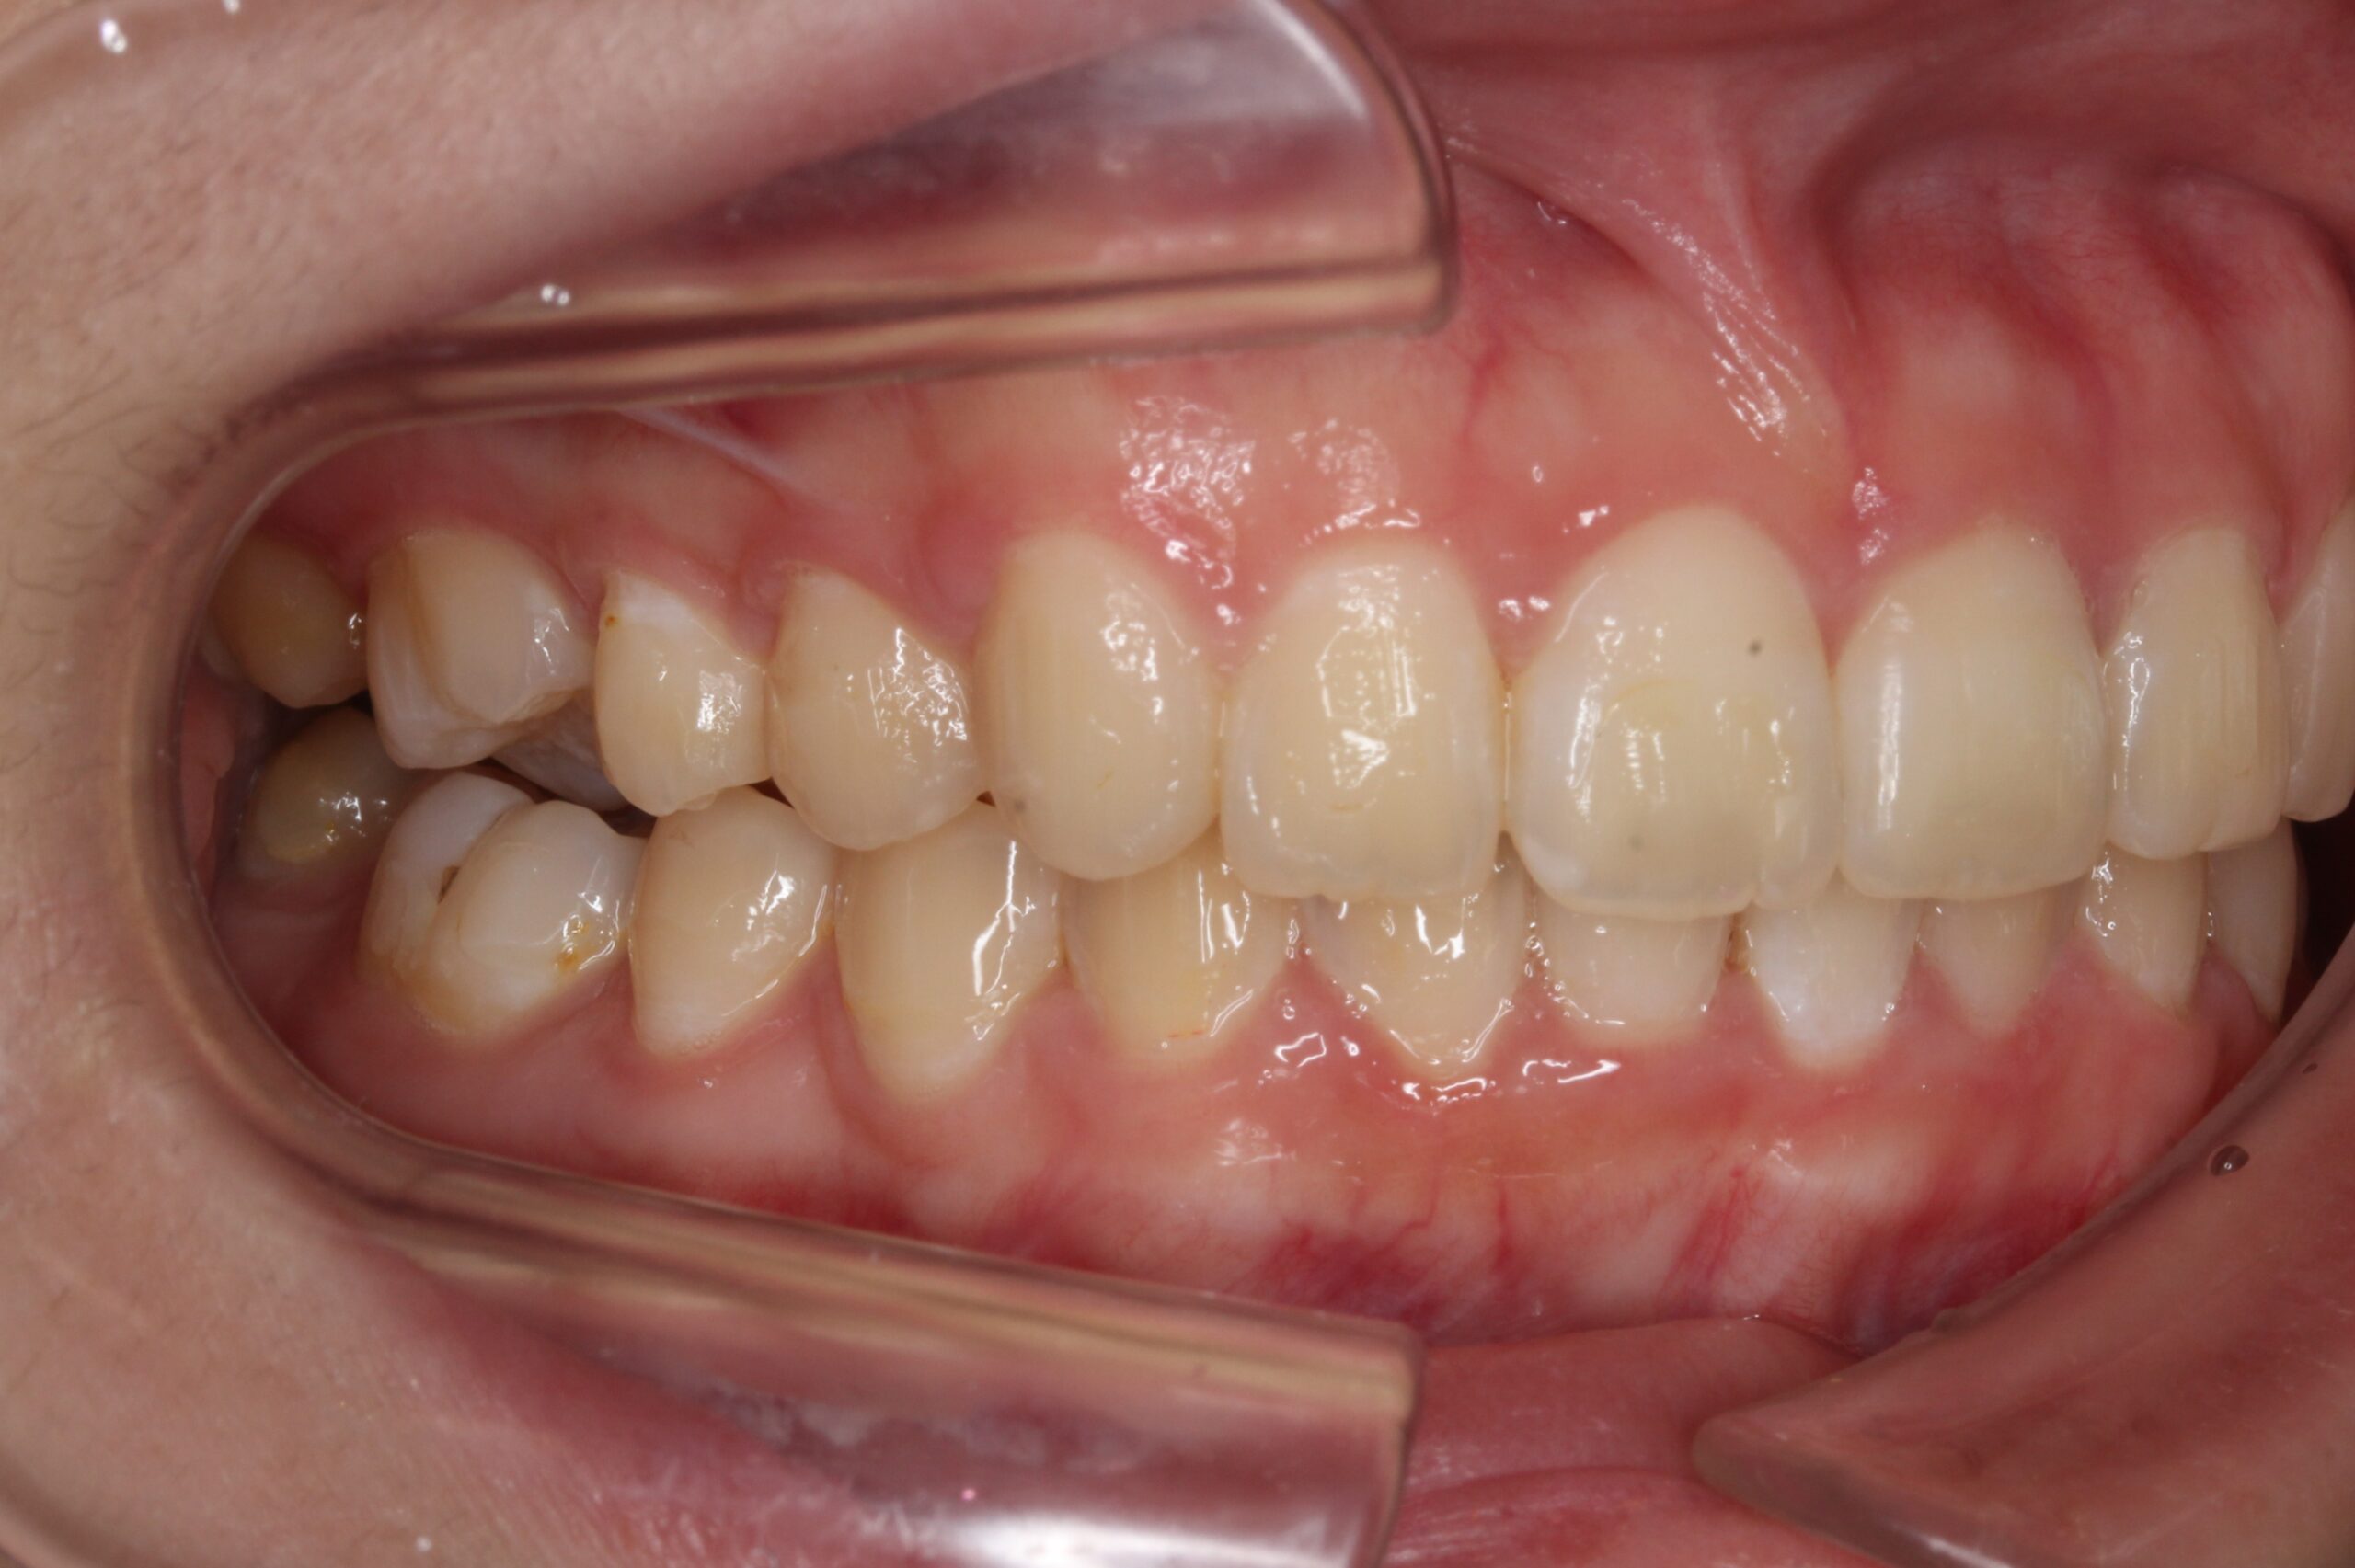

矯正術後:右側